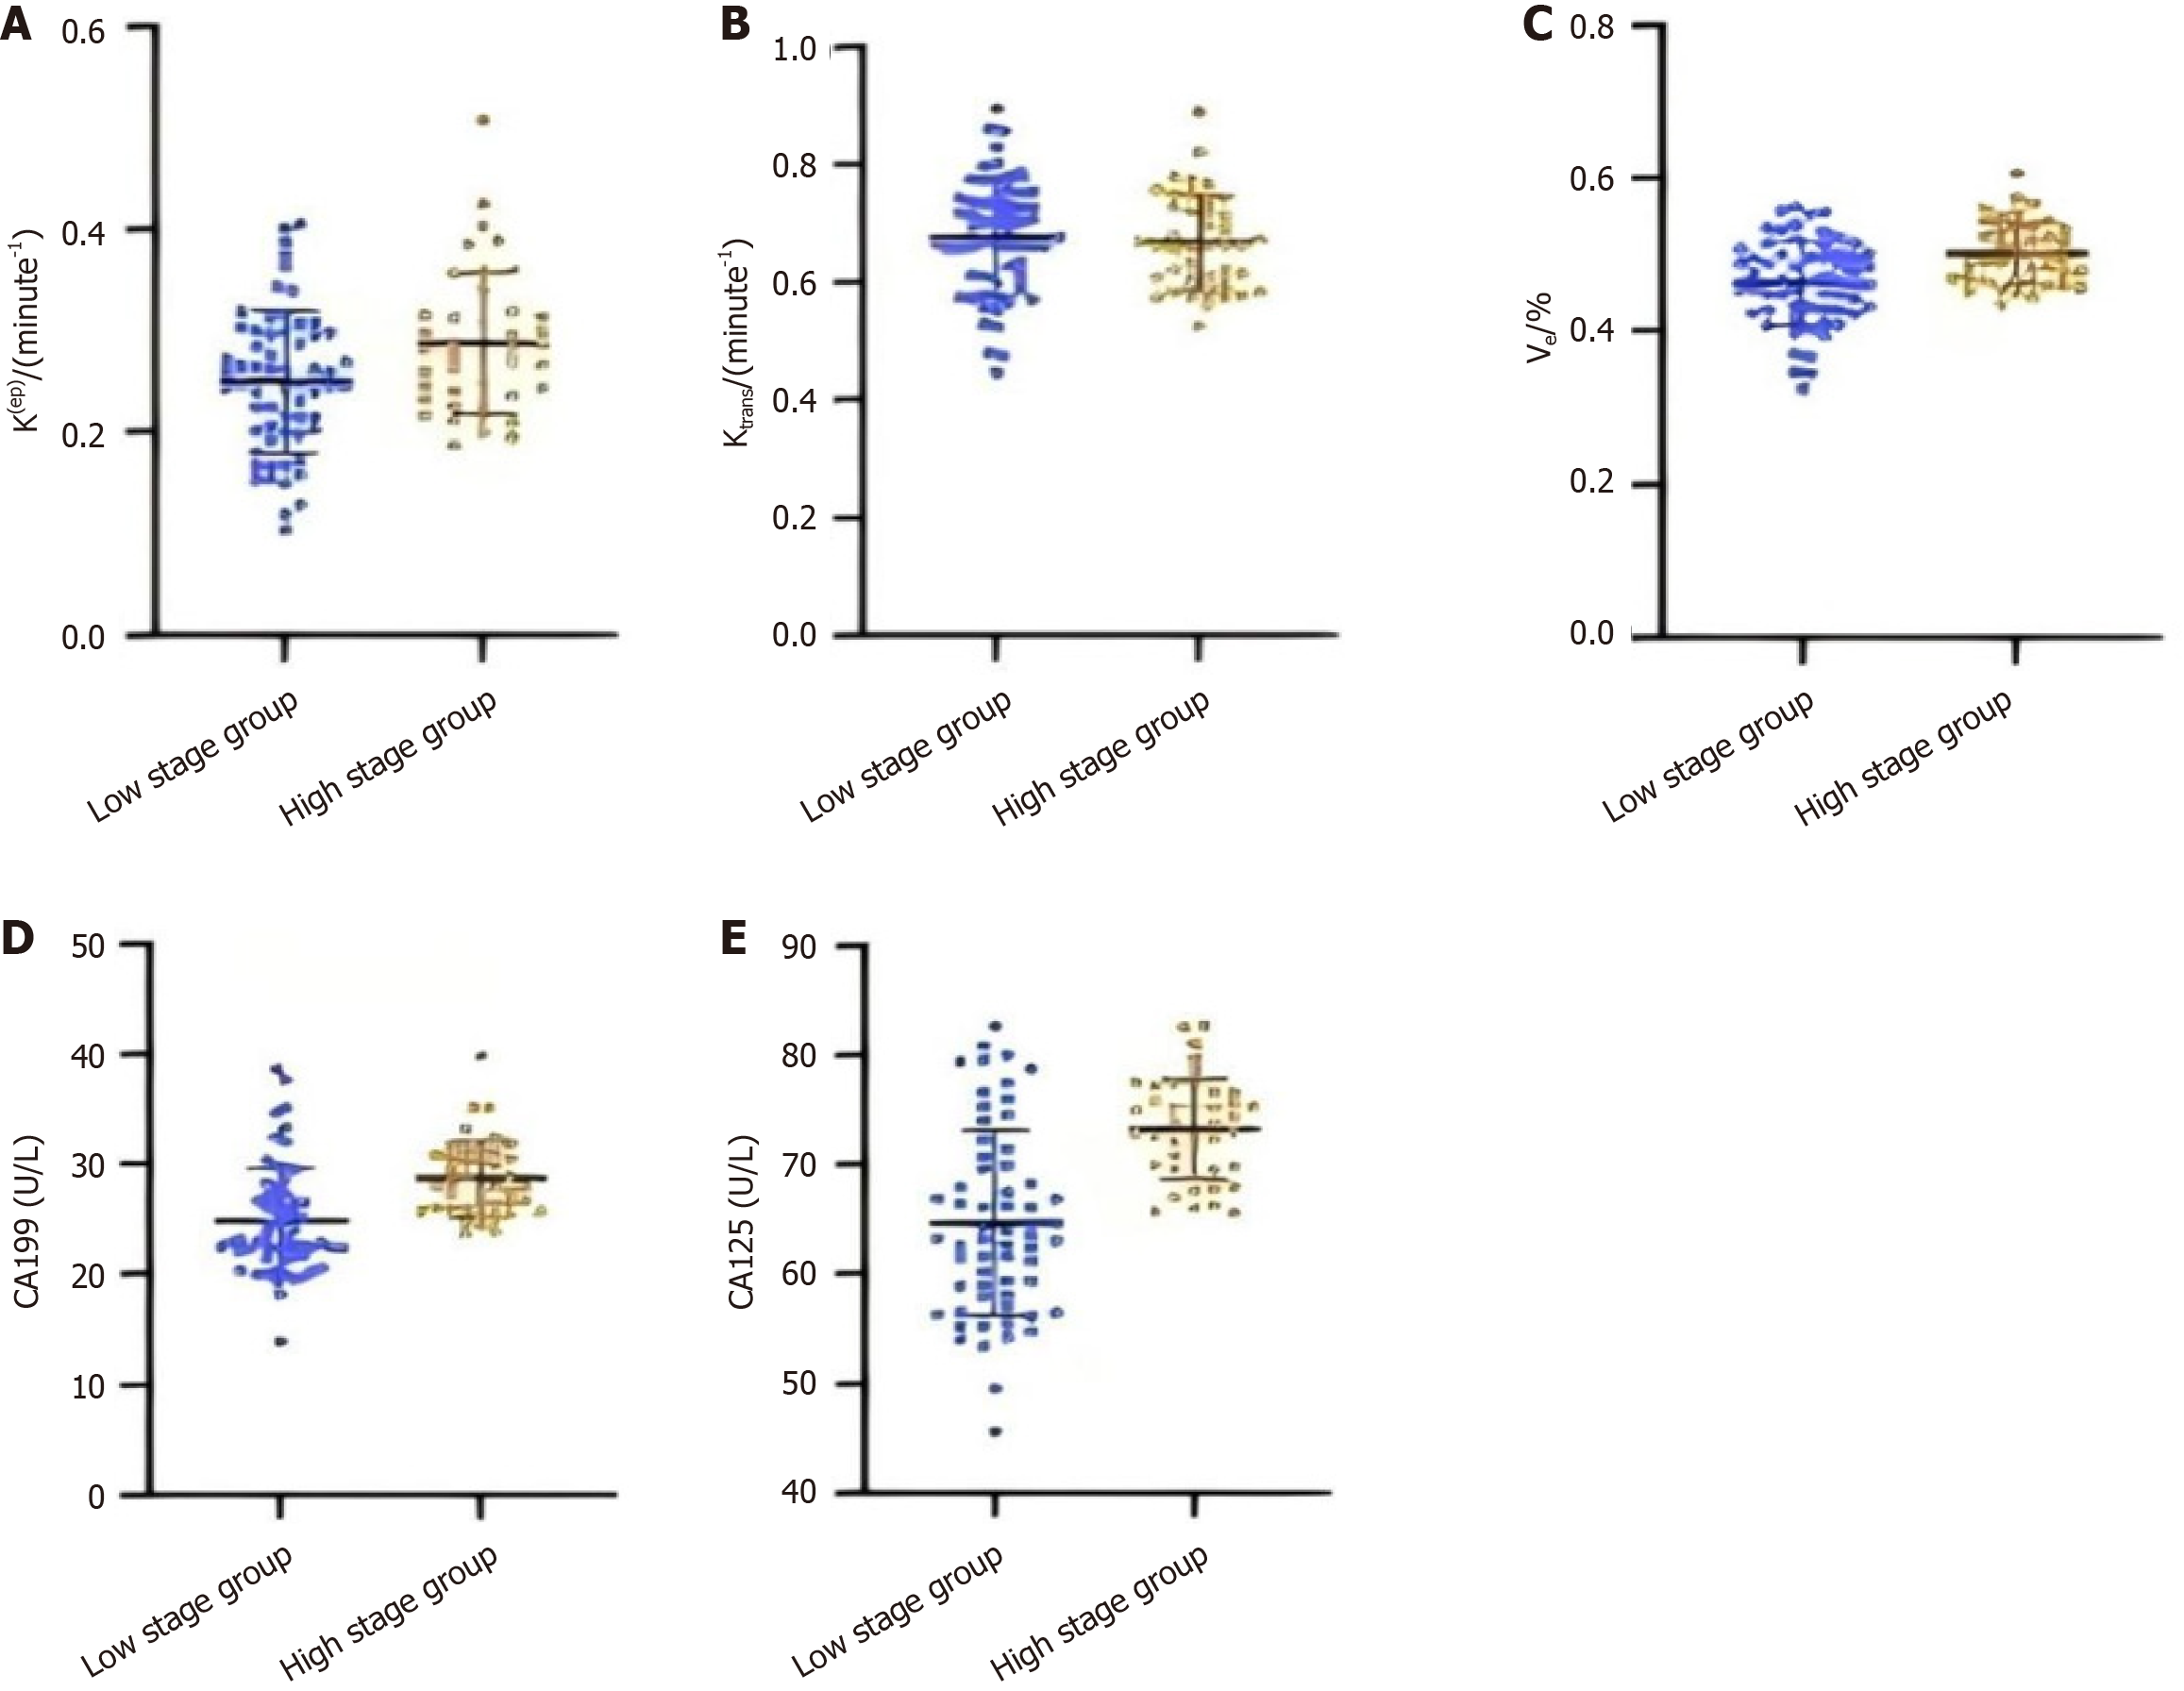

The findings from the study, as depicted in Figure 3, demonstrate that the Ktrans and Ve measurements are markedly elevated in the advanced T-stage cohort compared to the early T-stage cohort (P < 0.05). However, no significant discrepancy was observed in Kep values when comparing the two cohorts (P > 0.05). Concurrently, the serum concentrations of CA19-9 and CA125 were found to be considerably higher in the advanced T-stage group vs the early T-stage group (P < 0.05). These results may indicate a possible relationship between the T stage of rectal cancer and the DCE-MRI parameters (Ktrans and Ve) and serum markers (CA19-9 and CA125).